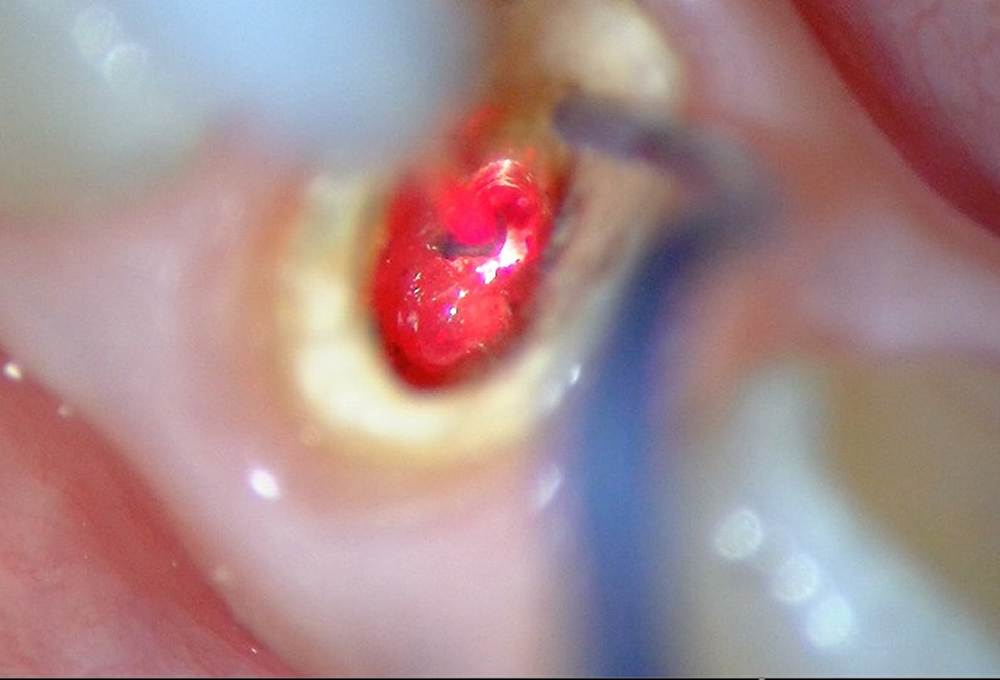

④YAGレーザーで根管内照射、殺菌